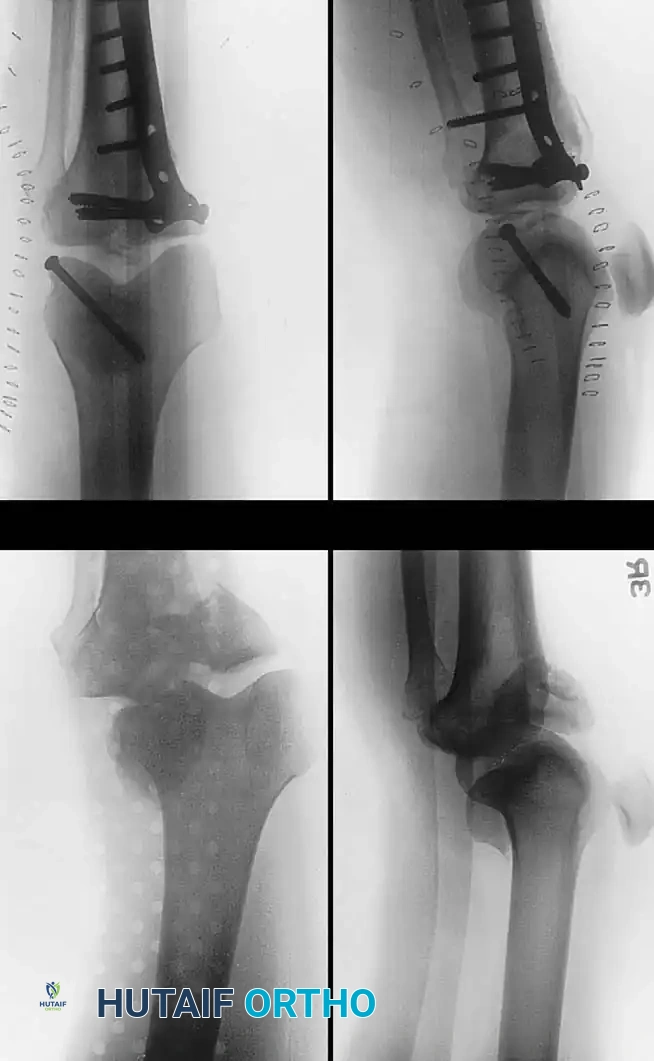

في الكسور المعقدة التي تشمل جانبي الركبة، غالبا ما يتطلب الأمر استخدام شريحتين معدنيتين لضمان عدم انهيار العظم تحت تأثير وزن الجسم.

استخدام شريحتين لتثبيت الكسور المعقدة

يقوم الجراح باستخدام جهاز الأشعة التداخلية للتأكد من استعادة المحور الميكانيكي للساق، والتأكد من عدم اختراق أي مسامير لسطح المفصل.

التصوير الإشعاعي أثناء الجراحة للتأكد من التثبيت

متابعة التئام الكسر بالأشعة بعد الجراحة

مراحل متقدمة من التئام كسر هضبة التيبيا